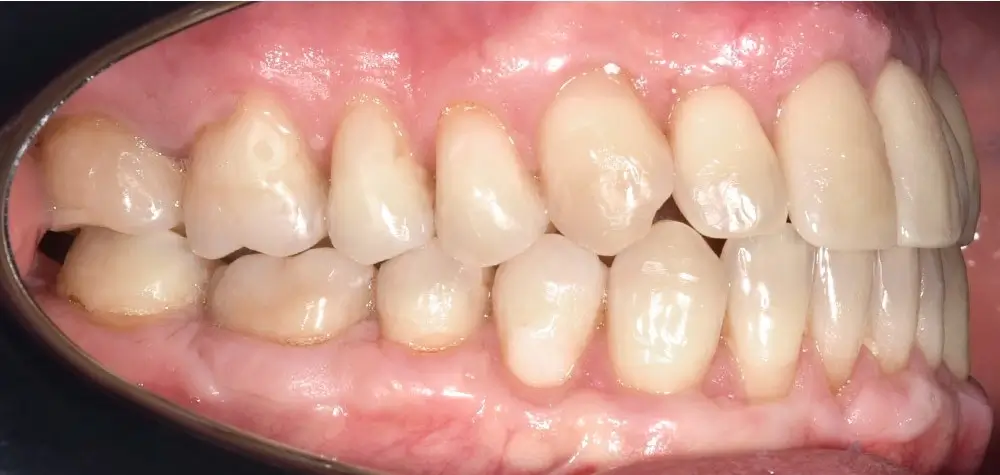

Мезиальный прикус - Кейс 7

Эффективность устранения дефекта прикуса посредством элайнеров FlexiLigner.

Результаты лечения